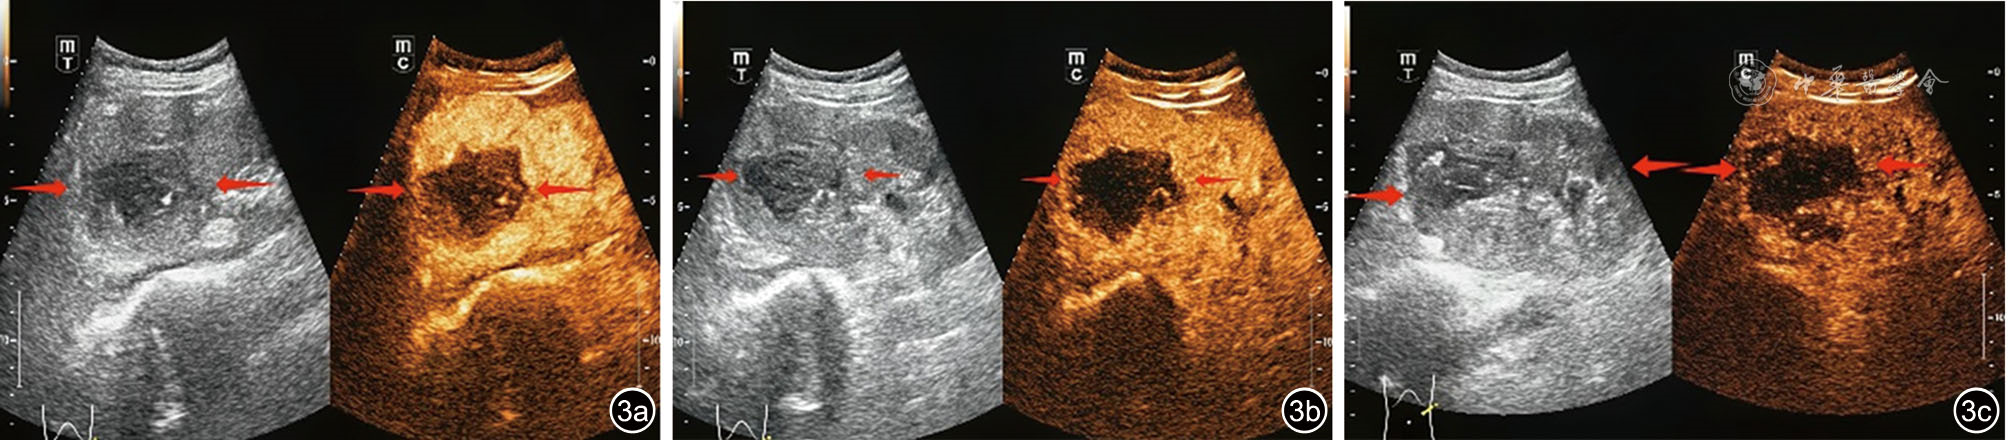

胡海, 万青, 王铮. VHL综合征超声表现1例并文献复习 [J]. 中国医学工程, 2024, 32(3): 131-132.